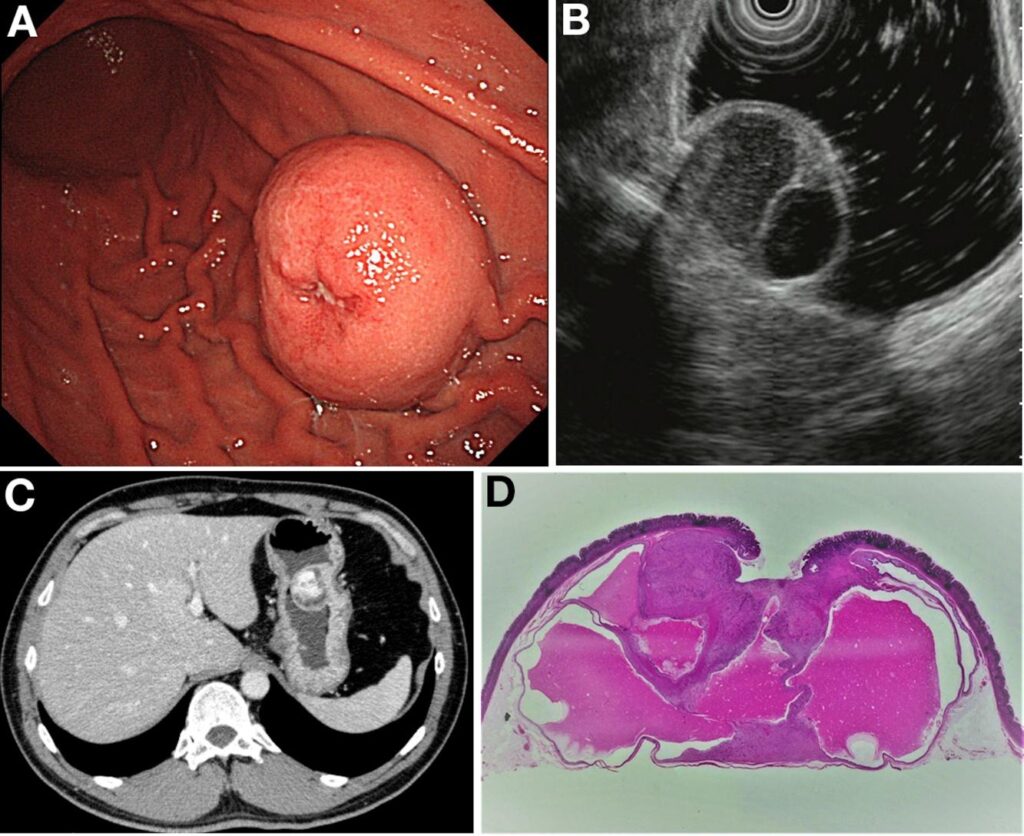

A:胃内視鏡、B:EUS、C:CT、D:病理組織診断(GIST症例)

胃内視鏡検査

胃粘膜下腫瘍のほとんどは、健診や定期検査の際の胃内視鏡検査で偶然発見されます。内視鏡(胃カメラ)を使用して直接観察し、腫瘍の部位、大きさ、形などを確認した上で胃粘膜下腫瘍と診断します。

超音波内視鏡検査(EUS)

EUSとは、胃カメラに超音波を出す装置がついたもので、組織の構造が変化する部位で音波が跳ね返ってくる現象(エコー)を利用して、跳ね返りの強さや部位を画像として映し出すことで、粘膜の下の構造、腫瘍を詳しく調べることができます。通常の胃カメラの検査よりも時間がかかるため、鎮静剤を使用して眠っている間に検査を行うことがほとんどです。

粘膜の下に存在する腫瘍の特徴を観察することで、より正確な診断が可能になります。

CT検査

X線を用いて体内の断層画像(輪切り画像)を撮影する画像診断技術です。身体の内部を描出するのに優れていて、病変の大きさ、リンパ節腫大の有無、他臓器への転移の有無の検索を行います。造影剤を点滴しながら行うこともあります。同じX線を使うレントゲン検査と比べて、得られる情報量は段違いなのですが、X線を大量に照射するため放射線被爆が伴います。もちろん被曝のリスクよりも、病気を見つけずに放置しておくことのリスクの方が大きい場合は、積極的に撮影することが必要です。